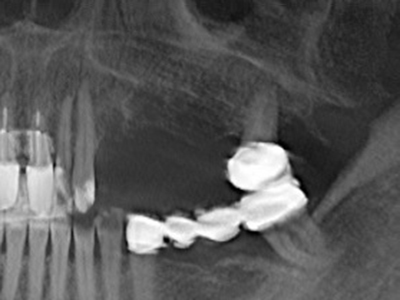

Bone tissue is not simply a mineral structure but also contains a substantial proportion of collagen fibres. This means it not only has good compressive strength but also a degree of flexibility, which can be taken advantage of when performing bone augmentations. In the classical expansion procedure using bone splitting, the atrophied alveolar ridge is split longitudinally and carefully expanded after reaching an adequate osteotomy depth (Fig. 13-16), ideally without substantial removal of the periosteum (Brugnami, Caiazzo et al. 2014, Stricker, Fleiner et al. 2014). Screw and plate systems with increasing expansion distance have proven effective in separating the two bone lamellae while remaining below the fracture threshold. In general, residual bone widths of at least 3–4 mm are required (Chiapasco, Zaniboni et al. 2006) to guarantee adequate flexibility and sufficient bone coverage of the future implants. If necessary, a vertical relief osteotomy on one or both sides can improve flexibility. A combination with additional augmentation techniques, particularly on the buccal side, has been described as an alternative to the classical technique.

The splitting procedure is particularly atraumatic and there is no significant loss of dimension when using piezosaws, and there are no significant differences between implants in split jaws and implants in an alveolar ridge without a bone deficit (Chiapasco, Zaniboni et al. 2006, Danza, Guidi et al. 2009). However, sufficient continuous irrigation is essential, particularly with locally restricted and deep splitting to prevent thermal stress in the apical osteotomy regions.